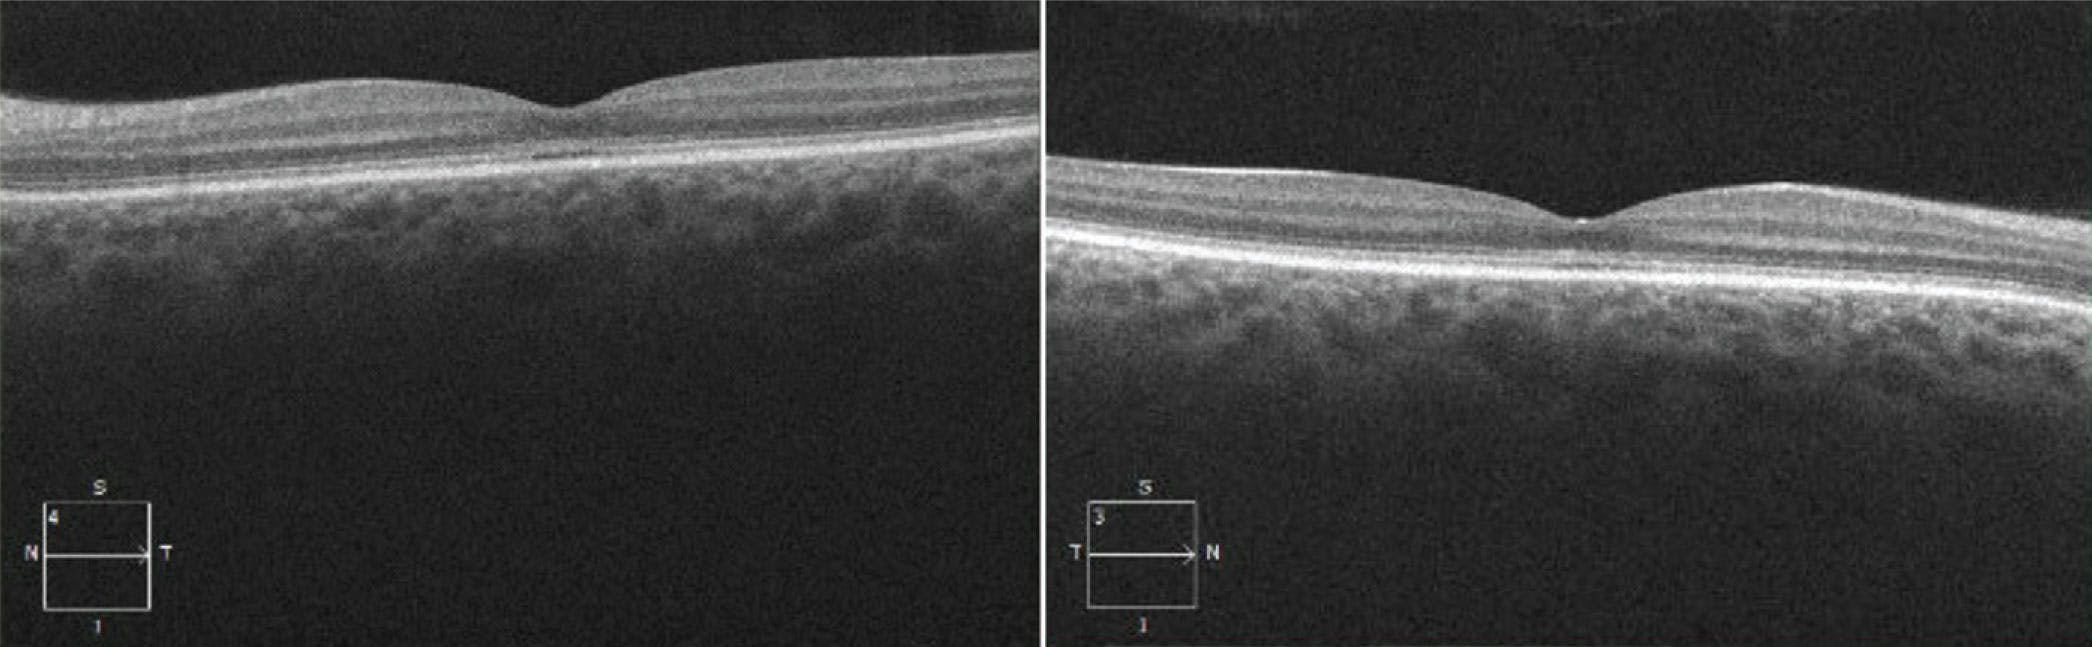

OCT allows for 3D dissection of the integrity of the individual retinal layers during the progression of IRD. Ellipsoid zone (EZ) disruption, RPE atrophy, outer retinal layer atrophy, and loss of the choriocapillaris are core OCT components of numerous IRDs. EZ disruption has garnered significant attention as a measure of disease progression and is being used as a clinical endpoint in RP trials and in investigations of complement inhibitors in Stargardt disease (NCT03364153).15,16 OCT can also assist with diagnosis and disease staging as seen in achromatopsia, which starts with EZ disruption followed by formation of optically empty space and eventual outer retinal loss (Figure 4).17

<p>Figure 4. OCT of the left and right eye of a 28-year-old woman with achromatopsia (homozygous for CNGB3 mutations) shows the beginnings of subfoveal EZ disruption and formation of optically empty space in each eye.</p>

Figure 4. OCT of the left and right eye of a 28-year-old woman with achromatopsia (homozygous for CNGB3 mutations) shows the beginnings of subfoveal EZ disruption and formation of optically empty space in each eye.